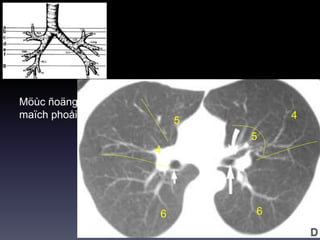

Möùc ñoäng

maïch phoåi T

maïch phoåi P

5

4

66